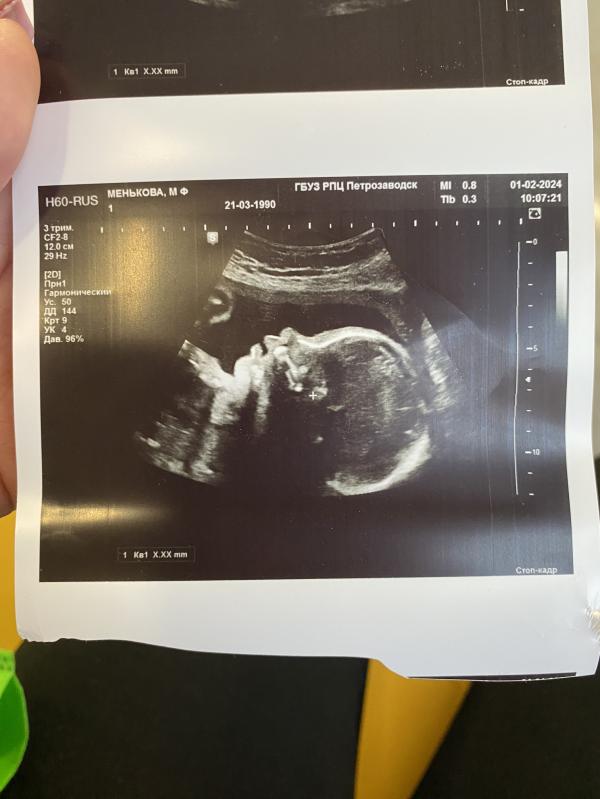

27,3😍🩷

Вес малышки 1045 гр.

Губастая моя 🥹